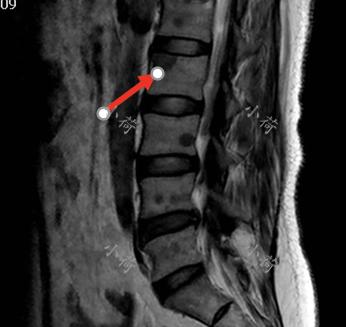

2018年,我第一次看到刘女士,是一位充满知性的女性,她确诊乳腺癌已经三年了,2015年发现左乳腺一个小小的肿物,就在我院乳腺外科完成了左乳腺保乳术加前哨淋巴结活检术,术后病理确诊为乳腺癌,进行了常规的化疗、放疗和内分泌治疗,不幸的是2018年夏天患者出现腰疼,检查提示发生了骨转移(图1),现在为了进一步治疗来到我的诊室。

图1 腰椎MRI显示椎体转移

患者入院后,我们首先给她进行了实验室检查,血常规、肝肾功能等其他实验室结果正常。接下来我们进行了影像学检查,骨扫描显示胸椎、腰椎部分椎体转移。乳腺超声、颈部CT均未见异常。我们对骨转移病灶进行了穿刺,病理:腺癌、考虑乳腺来源,ER(+)90%,PR(+)20%,HER-2(—),Ki-67 (+)30%。